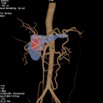

Pancreatic Mass & Abd VR

显示胰腺肿瘤、胰腺与腹部主动脉及其主要分支血管的相应关系

Pancreatic Mass & Abd Bone VR

染色后胰腺肿瘤、胰腺与腹主动脉及其主要分支血管的VR和腹部全影像相叠加的影像;显示胰腺肿瘤与腹部的脏器及骨骼的相应关系